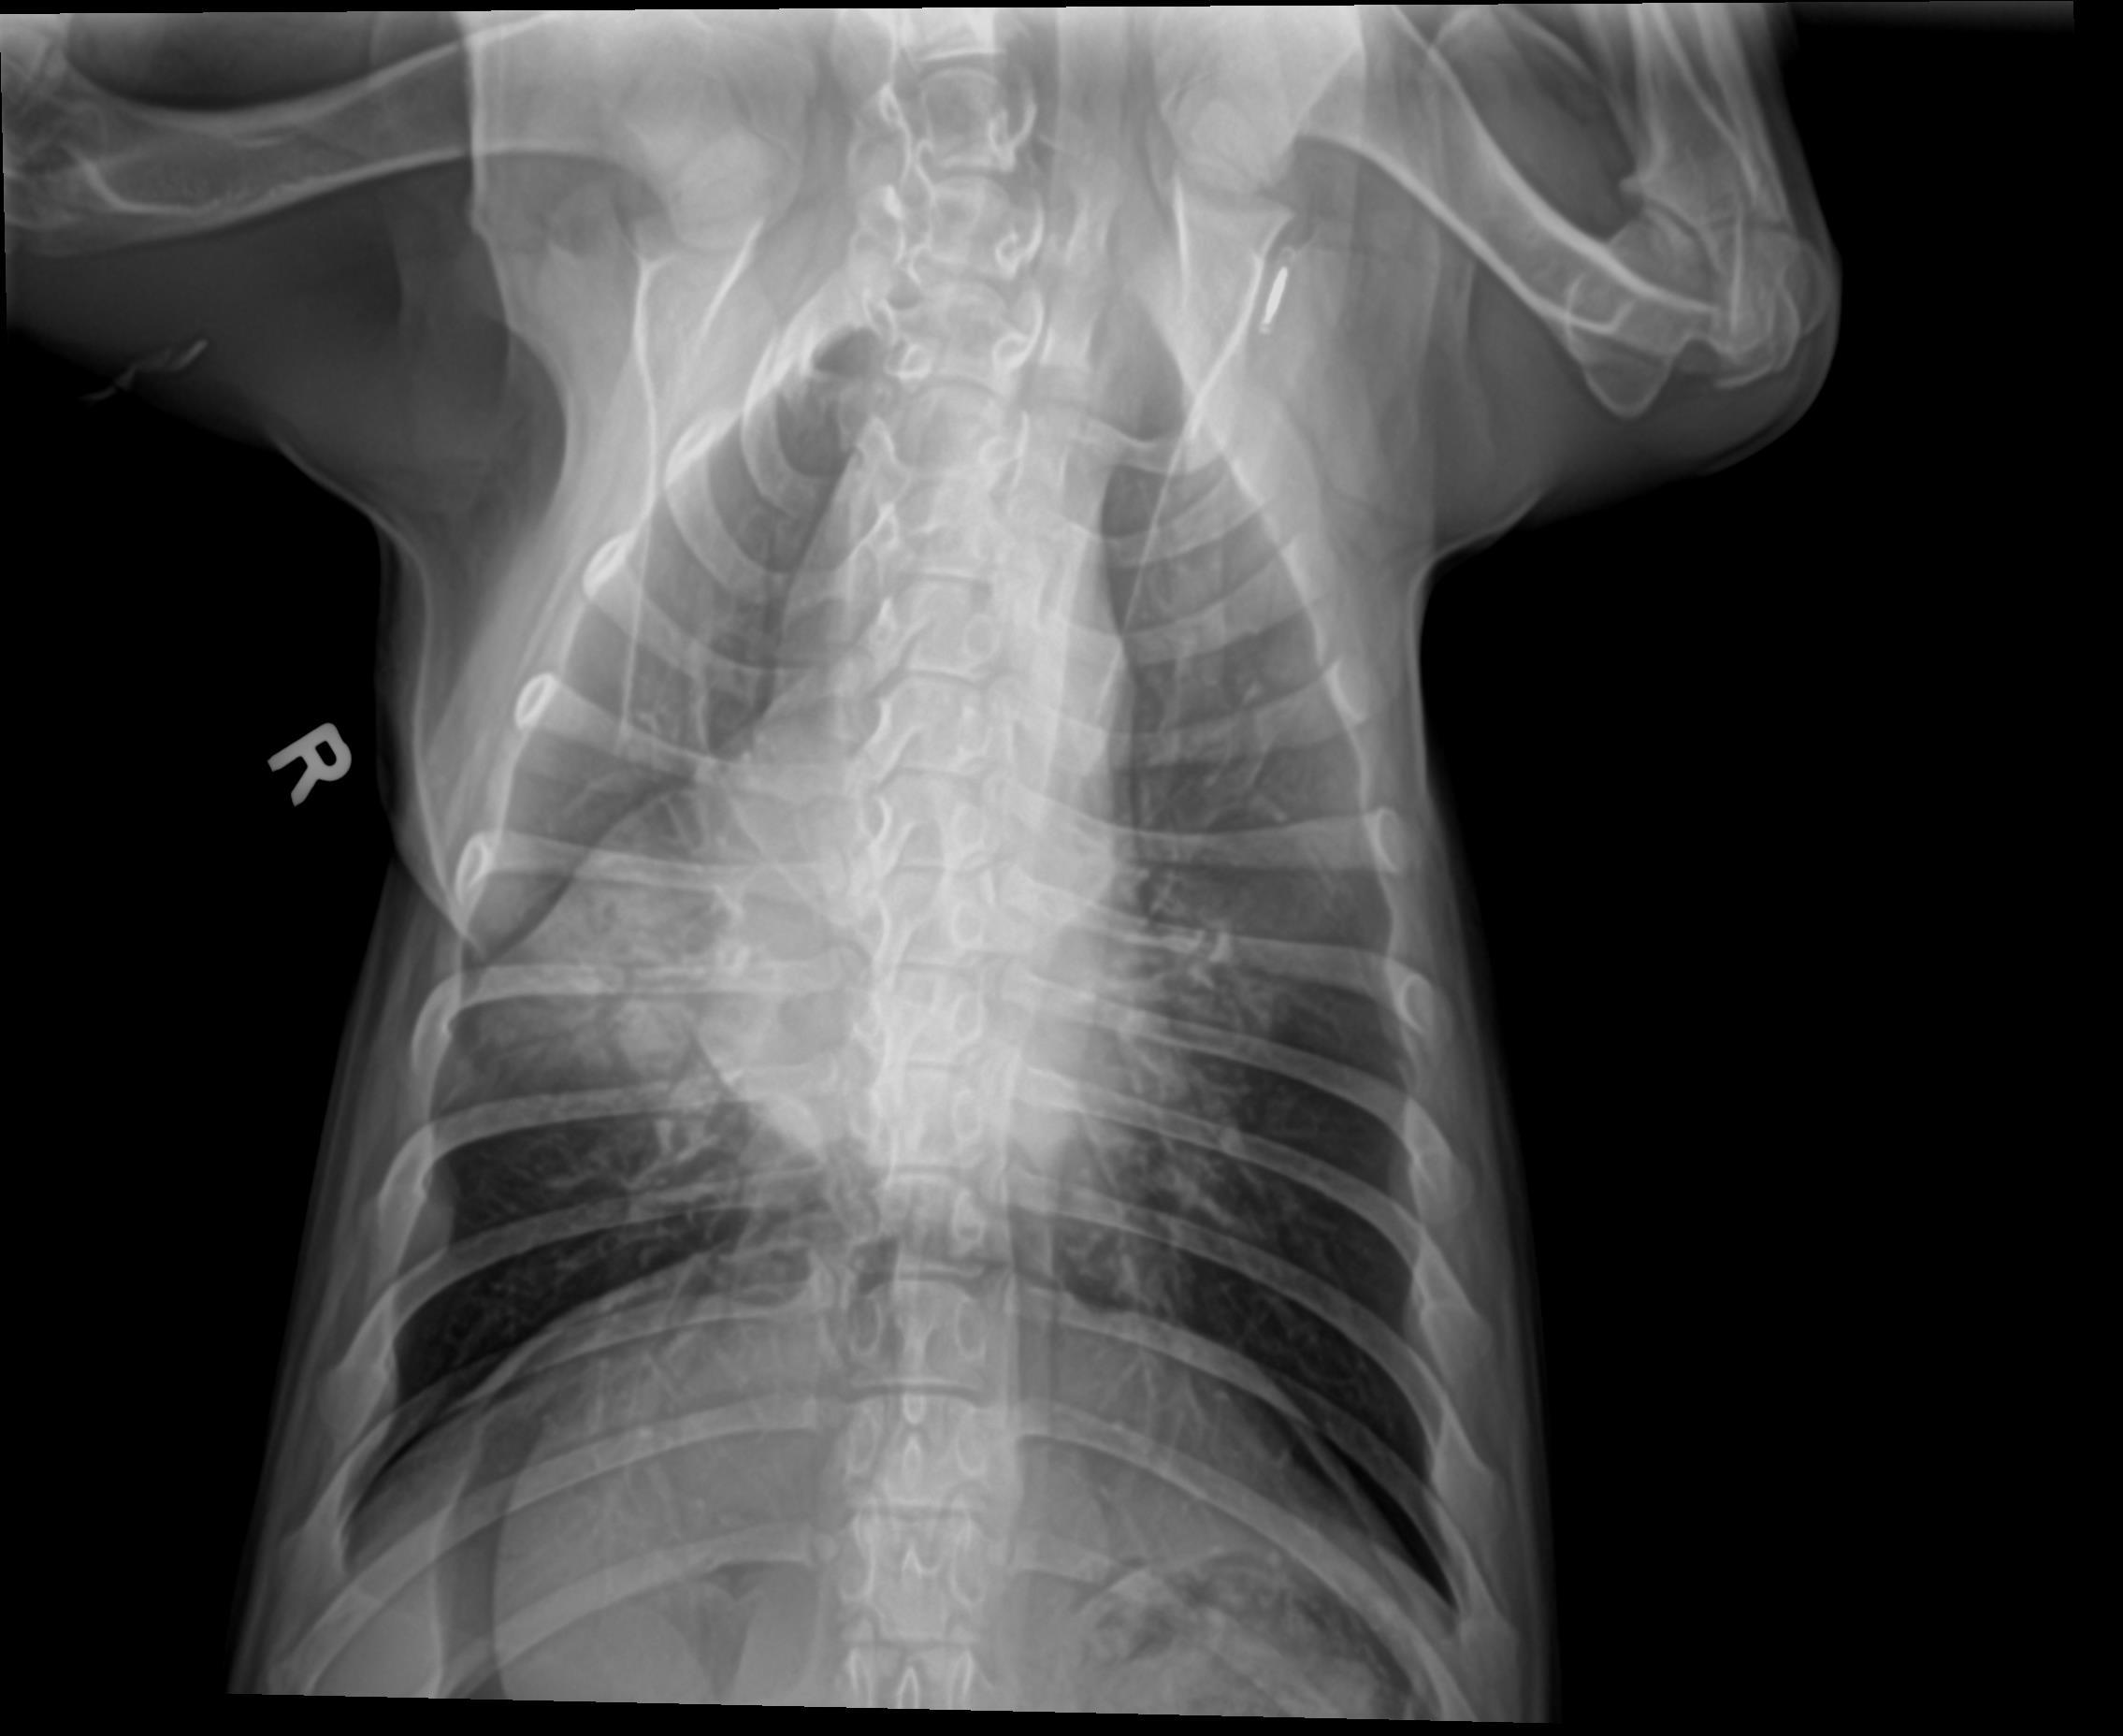

Physical exam findings and radiographs consistent with pneumonia.

Patient’s appetite and energy returned two days after starting additional therapy. Repeat radiographs at post-five days showed significant improvement as well.

Radiographs Before Treatments